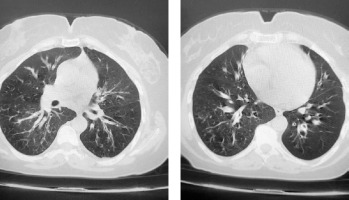

A 47-year-old female patient presented at our adult allergy and immunology outpatient clinic with complaints of cough, sputum production, and shortness of breath. Her medical history included asthma and allergic rhinitis for 15 years. The patient was using salmeterol fluticasone 500/50 µg 2 × 1, desloratadine 5 mg 1 × 1, montelukast 10 mg 1 × 1, and salbutamol inhaler 100 µg 4 × 1 for the diagnosis of asthma and allergic rhinitis. The patient has had two asthma exacerbations requiring oral corticosteroids (OCS) (at least 3 days or longer) in the last year. There was also a history of frequent antibiotic use due to frequently recurring pulmonary infections. Rhonchi were detected on both lungs during the physical examination. At the time of presentation at the clinic, the patient’s asthma was not under control, with an asthma control test (ACT) score of 5. In laboratory tests, total IgE, blood eosinophil count and house dust mite specific IgE level was high, and IgG2 and IgG4 levels were low. In flow cytometric analysis, CD3, CD4, CD8, CD16/56, CD19 values were within normal range. Both PR3 anti-neutrophil cytoplasmic antibody (ANCA) and MPO ANCA were detected negative. HIV serology was detected negative. Complete urinalysis examination and other laboratory tests were within normal range. Bronchiectasis in both lungs was determined on thoracic computed tomography (Figure 1). On paranasal sinus computed tomography, findings were consistent with widespread sinusitis in all paranasal sinuses (Figure 2). In the pulmonary function test, forced expiratory volume in 1 s (FEV1) was 34%, forced vital capacity (FVC) was 53%, and the FEV1/FVC ratio was 55%. The patient was diagnosed with uncontrolled hypereosinophilic severe persistent asthma and immune deficiency (immunoglobulin G subclass deficiency). The patient had frequent lung infections under antibiotic prophylaxis with trimethoprim-sulfamethoxazole 80/400 mg 3 days per week. Treatment was started of benralizumab 30 mg/subcutaneously once a month for the diagnosis of uncontrolled hypereosinophilic severe persistent asthma, and IVIG 30 g every 21 days for the diagnosis of immunodeficiency (ACT score at 1 year: 20). After 1 year of benralizumab treatment, improvements were observed in respiratory function tests (FEV1: 46%, FVC: 65% and FEV1/FVC ratio: 64%) and blood eosinophil count (at 12th month: 0 cell/ml). The IVIG treatment resulted in decreased antibiotic use for recurrent lung infections in the 1-year period. The clinical and laboratory findings of the patient are shown in Table 1.